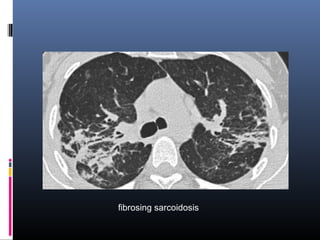

fibrosing sarcoidosis

• #43 a case of fibrosing sarcoidosis, showing fibrosis, traction bronchiectases and crowding of the involved bronchi, predominantly in the perihilar region and upper lobes. Nodular abnormalities are absent, but the appearance and the location of the fibrosis are very suggestive of the diagnosis of sarcoidosis.